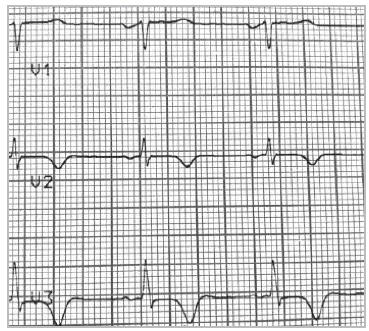

El electrocardiograma en reposo revelaba alteración de la repolarización ventricular, con T negativa profunda en V2 y V3, con QT corregido normal e hipertrofia ventricular izquierda (Figuras 1 y 2).

Figura 2 Signos de hipertrofia ventricular izquierda, con alteración de la repolarización y T negativa en derivaciones precordiales. Extrasistolia supraventricular y dupleta.

La sospecha diagnóstica se inicia con la toma de un electrocardiograma basal. Las características electrocardiográficas típicas son la hipertrofia ventricular, la presencia de ondas T negativas gigantes (≥ 10 mm), depresión del ST y ondas U negativas en DII, III y aVF, V4-V6 y QTc prolongado. En el presente caso, estos hallazgos se encuentran compatibles con el diagnóstico. Los hallazgos más frecuentes son la clásica inversión profunda de la onda T en las derivaciones precordiales hasta en 93% de pacientes y cerca del 65% de ellos presentan hipertrofia ventricular izquierda. Las ondas T negativas gigantes, se han reportado en 47% de los pacientes con esta patología 5. No obstante, se ha descrito que las ondas T gigantes no se evidencian constantemente en esta entidad, dado que estas y la depresión del segmento ST pueden variar con el paso del tiempo 6.